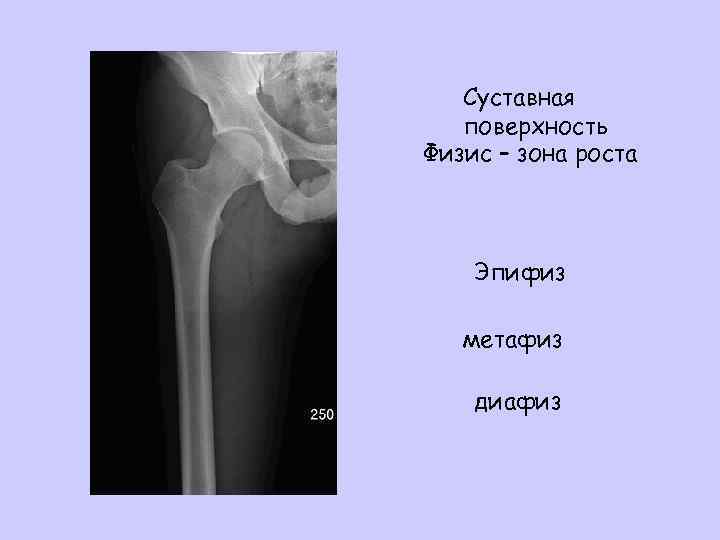

КАКОЙ ПЕРЕЛОМ? ! • Кости-то длинные – какая часть?

Суставная поверхность Физис – зона роста Эпифиз метафиз диафиз